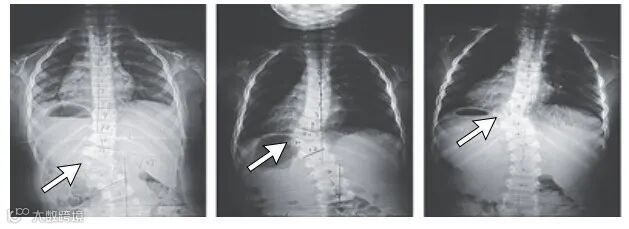

❺ SCDO5型(TBX6基因)

SCDO5型患者临床症状出现更早,以下半段脊柱的半椎体和蝴蝶椎为典型特征。